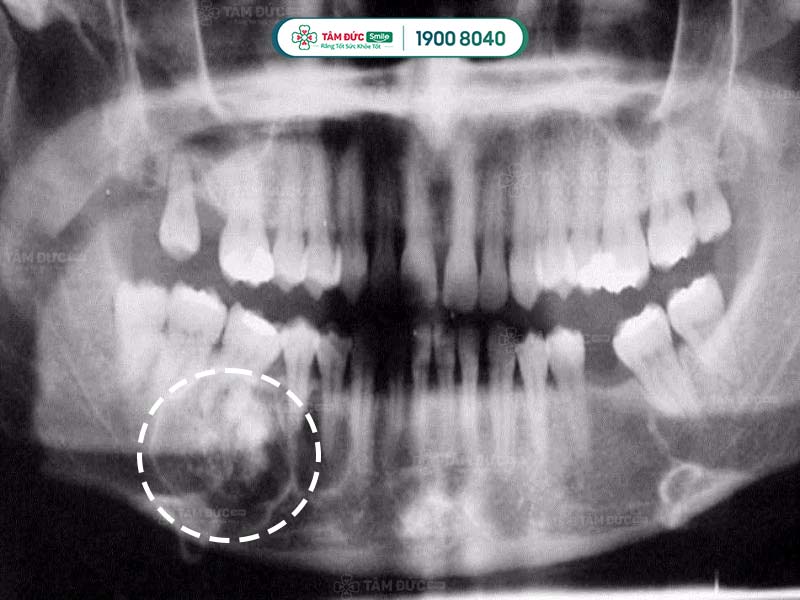

5.2. Chụp CT scan cho u răng

Sử dụng phương pháp chụp CT Scan để nhìn thấy rõ được cấu trúc bên trong khối u răng đó như thế nào.

Trong một số trường hợp cần thiết như u răng phức hợp phát triển vào khoang mũi. Cần thực hiện thêm 1 số xét nghiệm khác như chụp cộng hưởng từ MRI… Để có thể đưa ra được phương pháp điều trị phù hợp.